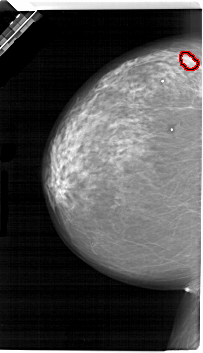

A_1657_1.LEFT_CC

LEFT_CC LINES 6691 PIXELS_PER_LINE 3856 BITS_PER_PIXEL 12 RESOLUTION 43.5 OVERLAY

FILE: A_1657_1.LEFT_CC.OVERLAY

TOTAL_ABNORMALITIES 1

ABNORMALITY 1

LESION_TYPE MASS SHAPE LOBULATED MARGINS OBSCURED

ASSESSMENT 4

SUBTLETY 3

PATHOLOGY MALIGNANT